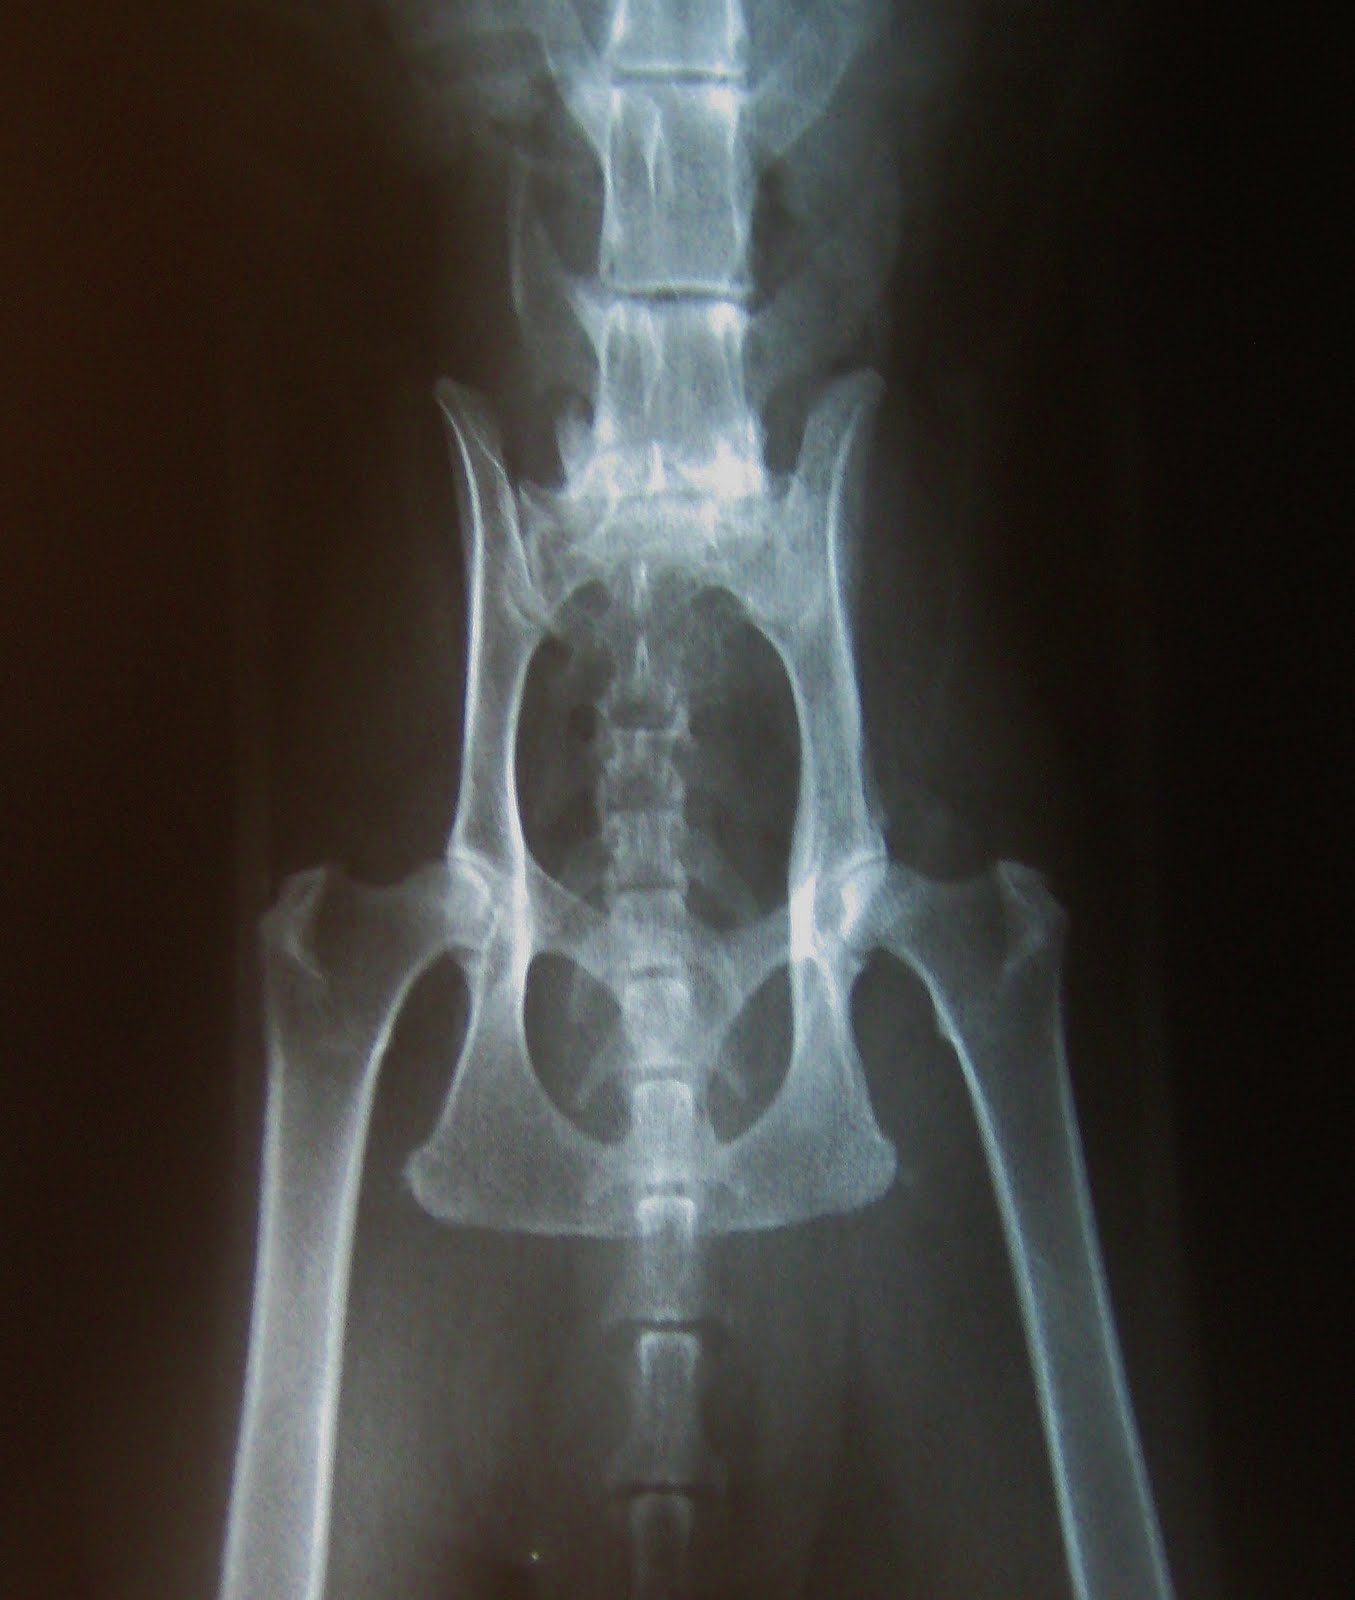

Arthritis Dog Xray . Osteoarthritis is a common problem in dogs, particularly in seniors and large breeds. Joint degeneration can be seen in both dogs and cats. Clinical signs of degenerative joint disease include lameness, joint swelling, muscle atrophy, pericapsular fibrosis, and crepitation. Infectious arthritis may extend into subchondral bone. Subchondral bone loss appears initially as a ragged margin of subchondral. Your veterinarian may suspect arthritis based on symptoms of pain and reduced mobility and physical examination. Here are the best ways to manage your dog's. Oa is diagnosed through a thorough physical examination, palpation (feeling with the fingers to localize pain and determine its intensity), and additional diagnostics, including. How will my veterinarian diagnose arthritis in my dog? Joint narrowing may be seen in severe cases with complete cartilage erosion, but is difficult to determine radiographically as the dog is not.

Osteoarthritis is a common problem in dogs, particularly in seniors and large breeds. Joint narrowing may be seen in severe cases with complete cartilage erosion, but is difficult to determine radiographically as the dog is not. Here are the best ways to manage your dog's. Clinical signs of degenerative joint disease include lameness, joint swelling, muscle atrophy, pericapsular fibrosis, and crepitation. Oa is diagnosed through a thorough physical examination, palpation (feeling with the fingers to localize pain and determine its intensity), and additional diagnostics, including. Subchondral bone loss appears initially as a ragged margin of subchondral. Your veterinarian may suspect arthritis based on symptoms of pain and reduced mobility and physical examination. Joint degeneration can be seen in both dogs and cats. How will my veterinarian diagnose arthritis in my dog? Infectious arthritis may extend into subchondral bone.